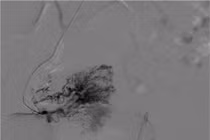

Ca can thiệp của chị T. được thực hiện bởi ê-kíp các bác sĩ Đơn vị Can Thiệp Mạch (Khoa Chẩn đoán Hình ảnh) Bệnh viện Đa khoa Xuyên Á. Thủ thuật diễn ra trong khoảng 1 giờ dưới sự hướng dẫn của máy chụp mạch số hóa xóa nền (DSA), người bệnh hoàn toàn không cần gây mê toàn thân (chỉ gây tê), không có vết mổ lớn, không chảy máu nhiều.

Nút mạch u xơ tử cung.

BS.CKI Trịnh Đình Hiếu, Đơn vị Can Thiệp Mạch, Bệnh viện Đa khoa Xuyên Á chia sẻ: “Trong quá trình can thiệp, chúng tôi đã chọc một lỗ nhỏ ở cổ tay và luồn một ống vi thông vào động mạch tử cung, sau đó bơm chất tắc mạch vào để chặn dòng máu nuôi khối u xơ. Khi không còn máu nuôi, các khối u sẽ teo nhỏ dần theo thời gian và không còn xảy ra các triệu chứng rối loạn”.

anh-chup-man-hinh-2025-09-16-075127.jpg

Nút mạch điều trị u xơ tử cung - Ảnh BVCC